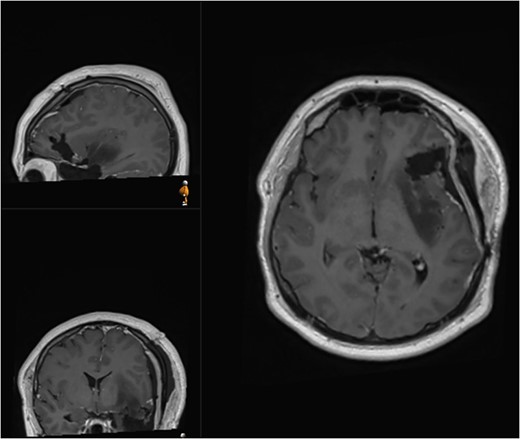

A 28-year-old right-handed man, with unremarkable past medical history, was admitted at the Emergency Department with generalized tonic-clonic seizure with complete post-ictal recovery. The imaging revealed a left frontotemporal insular lesion without contrast enhancement (Fig. 1). A first stage asleep-awake-asleep craniotomy was performed with no complications. The patient remained clinically well throughout admission without neurological deficit. Histology revealed Isocitrate dehydrogenase-mutant grade 2 astrocytoma. Post-operative MRI confirmed residual tumour (approximately 30%), leading to planification of a second-stage surgery.

Initial MRI demonstrating a non-contrast enhancing left frontotemporal insular lesion. (A) T1-weighted post contrast; (B) T2-weighted.